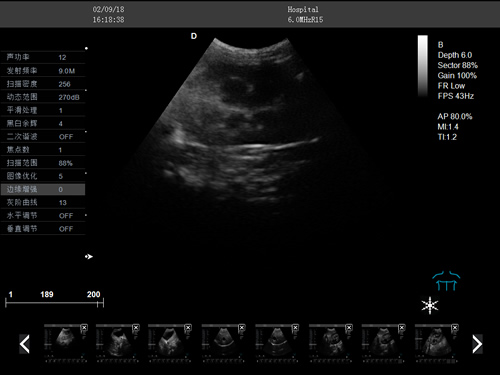

·支持彩色多普勒、頻譜多普勒、能量多普勒等成像技術

·組織諧波成像技術

·中小動物的肝、膽,脾、腎、膀胱、子宮、妊娠等各組織器官的檢查和病變的診斷